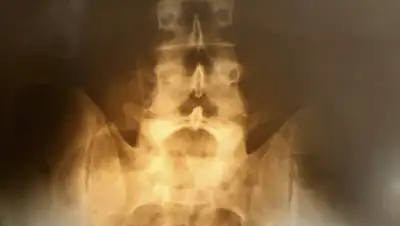

Ученым из Университета Нового Южного Уэльса в Австралии удалось превратить костные и жировые клетки взрослых людей в стволовые клетки, которые способны к регенерации любых тканей, включая сломанный позвоночник, передает Lenta.ru.

По словам исследователей, новая терапия имеет огромный потенциал для лечения спины и шеи, а также травм спинного диска, суставов и мышц.

Изображение: imagebroker / Michaela Begsteiger / Globallookpress.com